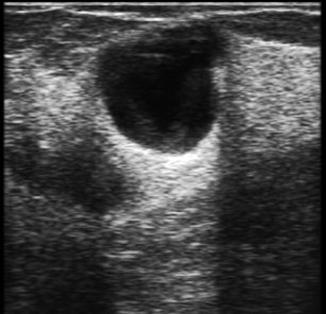

La presencia de una sola arteria umbilical se asocia hasta en un 10 a 15 % con malformaciones digestivas o génito-urinarias, por eso en un recién nacido con esta malformación vascular (arteria umbilical única) debemos solicitar una ecografía abdominal.

Figura 18. El cordón umbilical Corte transversal del cordón umbilical a la ecografía donde se evidencia el “Signo de Mickey Mouse” (AU: arteria umbilical, VU: vena umbilical)